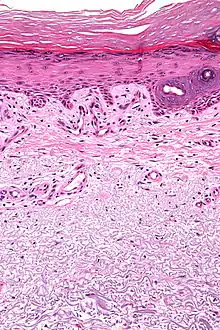

Micrograph showing solar elastosis - grey, jumbled spaghetti-like material on bottom of image. H&E stain.

Solar elastosis separates from the epidermis by a narrow band of normal-appearing collagen (grenz zone) with collagen fibers arranged horizontally.[1]

In the earlier stages of actinic elastosis, elastic fiber proliferation can be seen in the dermis. As the condition becomes more established, the collagen fibers of the papillary dermis and reticular dermis become increasingly replaced by thickened and curled fibers that form tangled masses and appear basophilic under routine haematoxylin and eosin staining. These fibers stain black with the Verhoeff stain.[2]